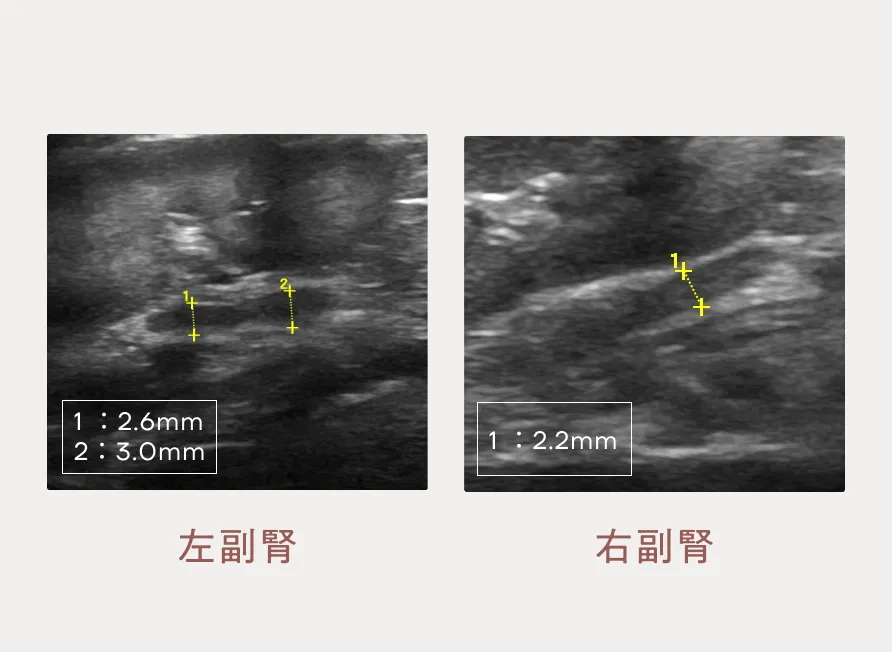

異物・アジソン病・びまん性胃腸疾患(慢性胃腸炎、リンパ管拡張症、リンパ腫)・ガストリノーマなどを鑑別疾患として念頭に入れ検査を行いました。身体検査と一般血液検査では何も異常がありません。エコー検査では胃の運動性低下、小腸の粘膜面は軽度に不整でやや腸管の腫れもみられます。特に気になったのは副腎が小さいことです。(図1・2)異物を疑う所見がないため、次にホルモン検査を行うと低値を示し、ホルモン分泌不足が認められ、「非定型アジソン病」と診断しました。